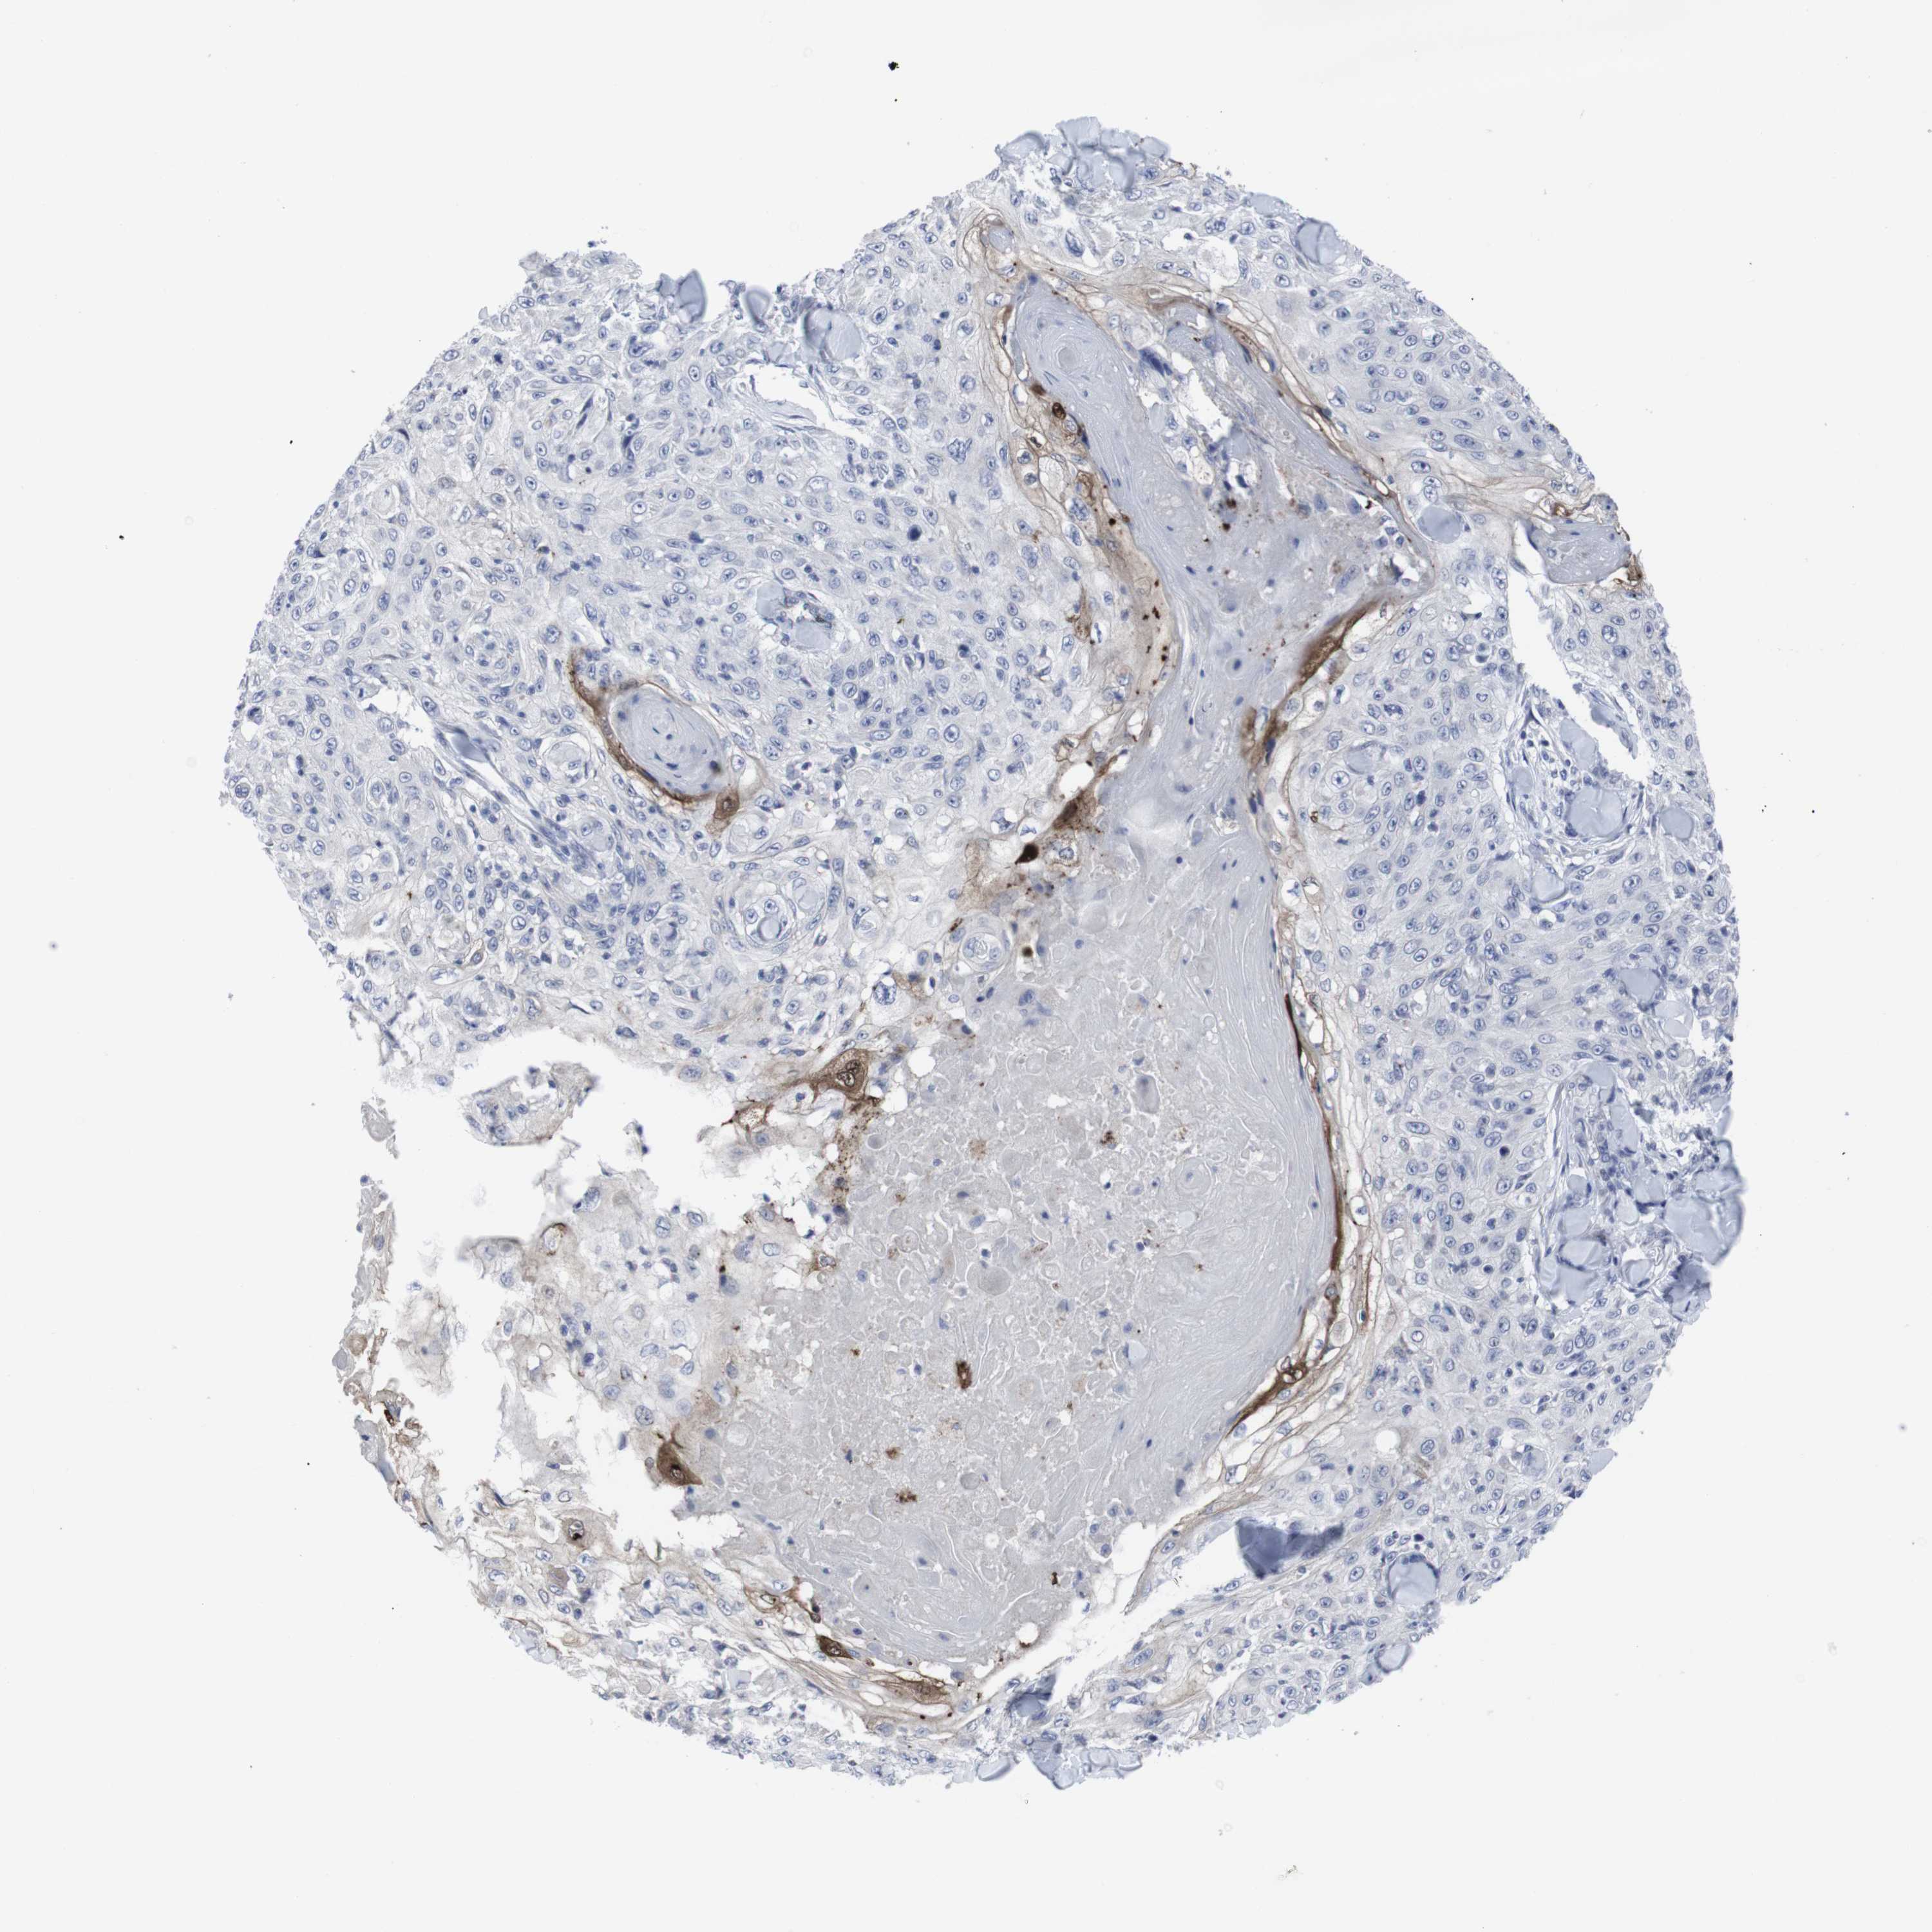

SKIN CANCER - Protein expressioni

A mouse-over function shows sample information and annotation data. Click on an image to view it in a full screen mode. Samples can be filtered based on level of antibody staining by selecting one or several of the following categories: high, medium, low and not detected. The assay and annotation is described here.

Each image is clickable and will lead to virtual microscopy that enables deeper exploration of all samples and also displays staining intensity scores, fraction scores and subcellular localization as well as patient and tissue information for each sample.

Antibody HPA014404

Squamous cell carcinoma, NOS